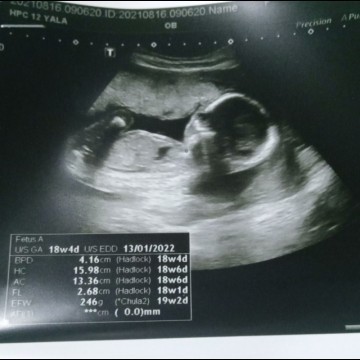

18w4d 246g หนักไม่ถึง3ขีด ถือว่า นน.ตามเกณฑ์ปกติค่ะแม่ ไม่ได้ตัวใหญ่มาก จากภาพที่เห็นว่าตัวใหญ่คือการซูมรูปมากว่าค่ะ

น้องไม่ได้ตัวใหญ่อะไรมากหรอกค่ะแม่ เป็นระยะซูมของเครื่องซาวค่ะ น้ำหนักน้อง 246 กรัมคิดว่าปกตินะคะ